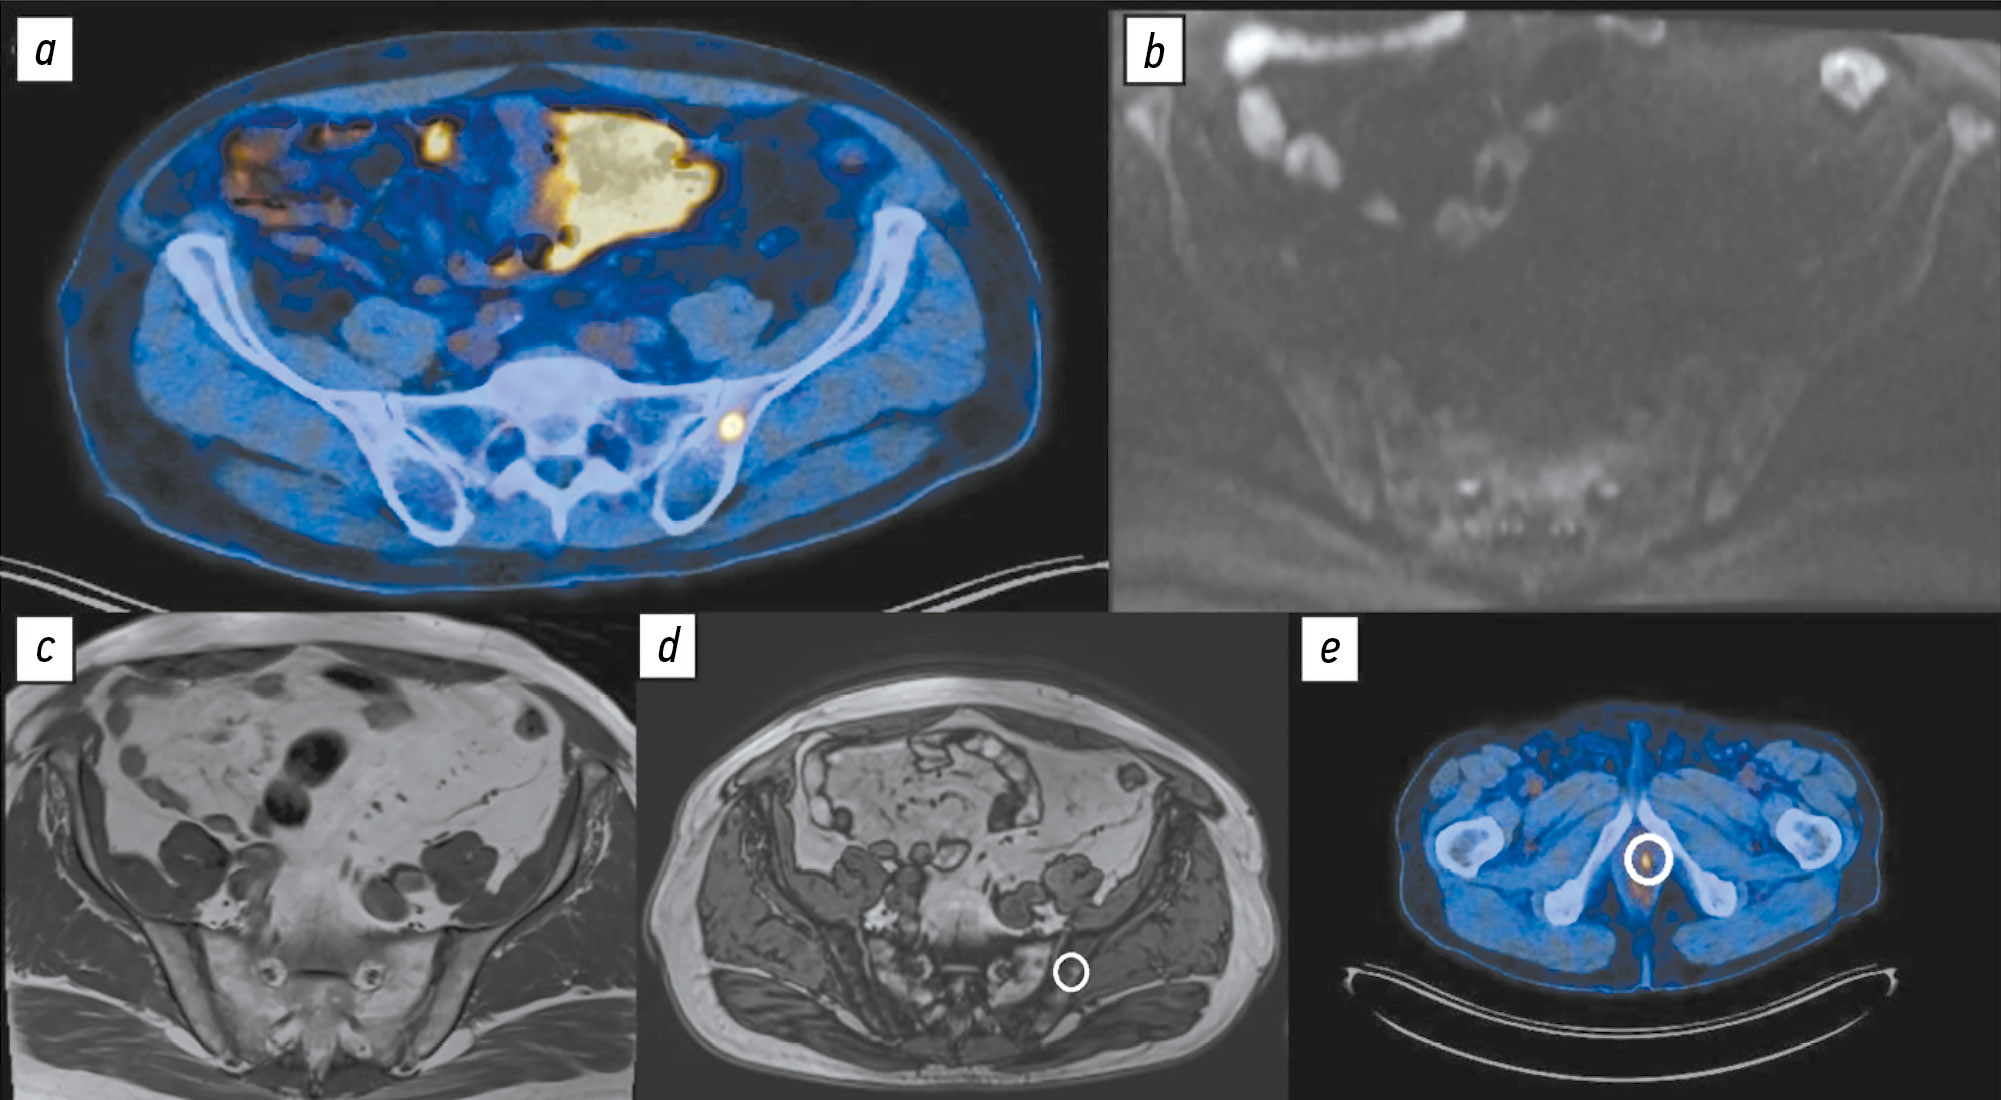

Полученные результаты свидетельствуют о низкой специфичности ПЭТ/КТ с 18F-ПСМА-1007 и ДВИ всего тела для выявления метастатического поражения костей, что подтверждено актуальными клиническими исследованиями, в частности многоцентровыми. Так, H. Grünig и соавт. [21] сообщают, что у 51,4% пациентов, проходивших ПЭТ/КТ с 18F-ПСМА-1007, обнаруживают очаги гиперфиксации в костях, клиническая интерпретация которых затруднена из-за их неопределённой природы. В одной из первых опубликованных работ, посвящённых сравнению диагностической точности ПЭТ/КТ с 18F-ПСМА-1007 и 68Ga-ПСМА-11, обнаружены значительные различия в частоте ложноположительных находок в скелете — 48 и 14,7% соответственно. Данный феномен традиционно объясняют более продолжительным периодом полураспада 18F по сравнению с 68Ga, что приводит к повышению пространственного разрешения и лучшему соотношению сигнала и шума [9]. Иммуногистохимический анализ показал наличие ПСМА не только в ткани предстательной железы, но и в очагах воспаления и неоангиогенеза [22]. Кроме того, РФП на основе ПСМА способны связываться и с доброкачественными процессами в костной ткани (рис. 1), такими как островки гиперплазии красного костного мозга, часто выявляемые в рёбрах [23], а также в гемангиомах тел позвонков [24]. Интерпретация магнитно-резонансной семиотики типичных гемангиом тел позвонков не вызывает затруднений и позволяет их дифференцировать от метастазов рака предстательной железы, однако «атипичные» гемангиомы зачастую требуют гистологической верификации [25]. Точный механизм фиксации РФП на основе ПСМА в доброкачественных структурах костной ткани остаётся неясным.

Рис. 1. Пациент А 56 лет со смешанной нейроэндокринной карциномой предстательной железы T3aN1Mx, Глисон 8 (4+4). Состояние после радикальной простатэктомии. Повышение содержания общего простатоспецифичного антигена сыворотки крови до 1,87 нг/мл. Рецидив опухоли в области везикоуретерального анастомоза: а ― изображение позитронно-эмиссионной компьютерной томографии в аксиальной плоскости: в теле левой подвздошной кости выявлен очаг гиперфиксации радиофармацевтического препарата, подозрительный в отношении метастатического процесса; b и с ― по данным диффузионно-взвешенного (b) и Т1-взвешенного изображений без жироподавления (с) очаговых изменений левой подвздошной кости не выявлено; d — по данным Т1-взвешенного изображения с селективным жироподавлением в области очага гиперфиксации радиофармацевтического препарат выявлена зона выпадения сигнала, соответствующая реконверсии красного костного мозга, патологических инфильтратов костного мозга не выявлено; e — очаг гиперфиксации по данным позитронно-эмиссионной компьютерной томографии с 18F-простатоспецифичным мембранным антигеном-1007 в области везикоуретрального анастомоза.